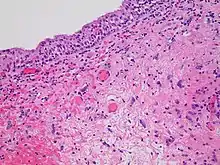

- Radiation necrosis

- Radiation necrosis is the death of healthy tissue near the irradiated site. It is a type of coagulative necrosis that occurs because the radiation directly or indirectly damages blood vessels in the area, which reduces the blood supply to the remaining healthy tissue, causing it to die by ischemia, similar to what happens in an ischemic stroke.[42] Because it is an indirect effect of the treatment, it occurs months to decades after radiation exposure.[42] Radiation necrosis most commonly presents as osteoradionecrosis, vaginal radionecrosis, soft tissue radionecrosis, or laryngeal radionecrosis.[5]